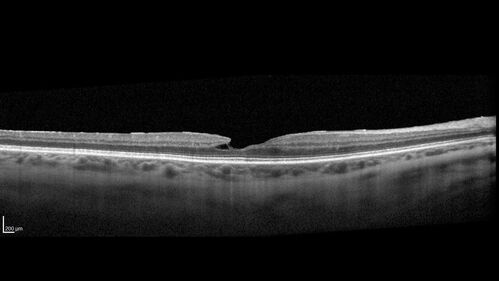

Lamellar Macular Hole and Good Vision

67 year old woman with good vision and floaters - VA 20/32 OD, 20/23 OS